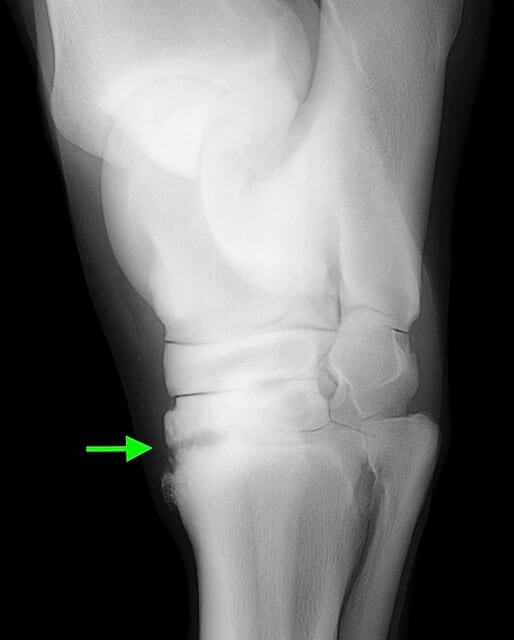

Michael Porter, Equine Veterinarian Hock Arthritis in a Horse Bone Spur In Horse Hock what we learned was a shock: It is a change in the normally smooth edge of the end of the bone. disorders of the tarsus (hock) include the conditions known as bog spavin, bone spavin, and curb. His hock had been broken and now has healed with what the veterinarian is. a bone spur forms near the. Bone Spur In Horse Hock.

Michael Porter, Equine Veterinarian Hock Arthritis in a Horse Bone Spur In Horse Hock a bone spur forms near the edge of a joint surface. bone spavin is osteoarthritis, or the final phase of degenerative joint disease (djd), in the lower three. It is a change in the normally smooth edge of the end of the bone. The tarsus can also be. disorders of the tarsus (hock) include the conditions known. Bone Spur In Horse Hock.